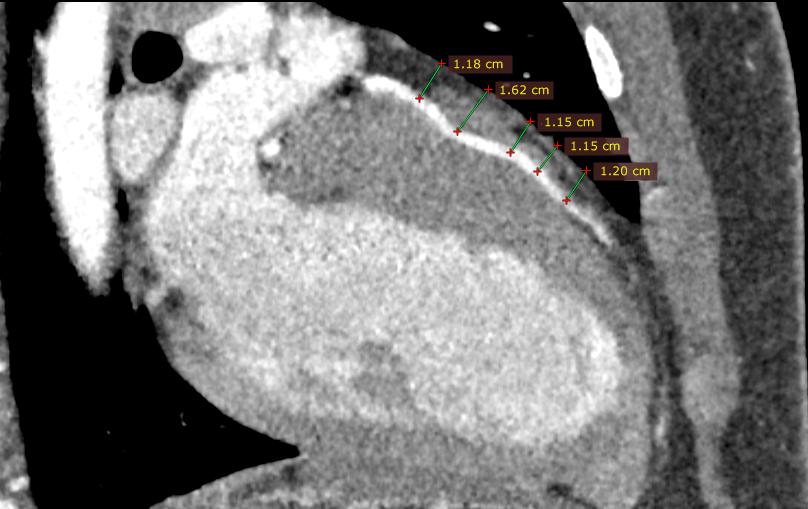

На рисунке показаны серии компьютерной томографии сердца пациента с миокардиальным мостиком передней межжелудочковой артерией (до операции). Стрелками обозначен наиболее глубоко проходящий сегмент артерии. |